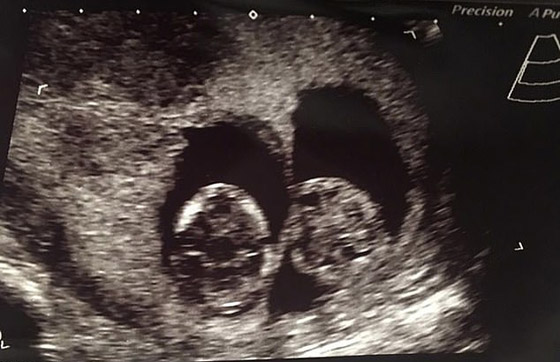

حسب تقرير لصحيفة بريطانية، الثلاثاء، فإن التوأمين، أصبح لديهما أعياد ميلاد مختلفة، أما السبب فيعد لكونهما رأيا النور في منتصف الليل. في تعليقها على الأمر تقول الأم كريستن: "طوال حملي، قيل لي إنهما غير متطابقين، وقد آمنت بذلك"، لكن بعد ولادتهما في 6 و7 يونيو/حزيران، بَدَآ يبدوان متشابهين للغاية. وقد كانت هناك فرصة بنسبة 30% فقط أن يكونا متطابقين بسبب وجودهما في كيسين منفصلين.

لكن الأم تقول إن الجميع واجه صعوبات كبيرة ليتمكن من التمييز بينهما وقررت إجراء اختبار جيني للاختبار، وهو ما أكد التماثل. كما قيل لكيرستن إن هوغو وليو توأمان ثنائيا المشيمة، مما يعني أن كل توأم له أكياس مشيمية وسلوية خاصة به، وهو الأكثر شيوعاً في التوائم غير المتماثلة. وهذا بالضبط ما أظهرته النتائج، وتضيف أيضاً: "بعد أن اطلعنا على الأخبار، كنا سعداء للغاية".